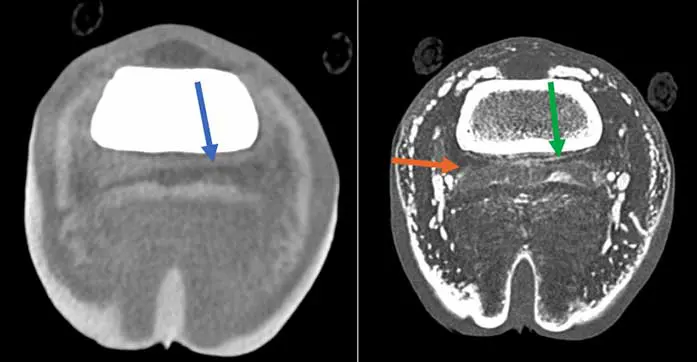

One of the main advantages of using standing CT is the ability to scan more than one region at a time as opposed to MRI. This is particularly advantageous for DDFT lesions, as it is recognised that very often it affects more than one region – foot and pastern or fetlock, for example (Figure 3) – and for horse with equivocal blocking pattern. Additionally, the use of IV or intrathecal contrast has improved the soft tissue enhancement capacity of CT, making it attractive to identify most distal limb tendinopathy (Figure 4), and has increased ability to diagnose mineralisation compared to MRI13.